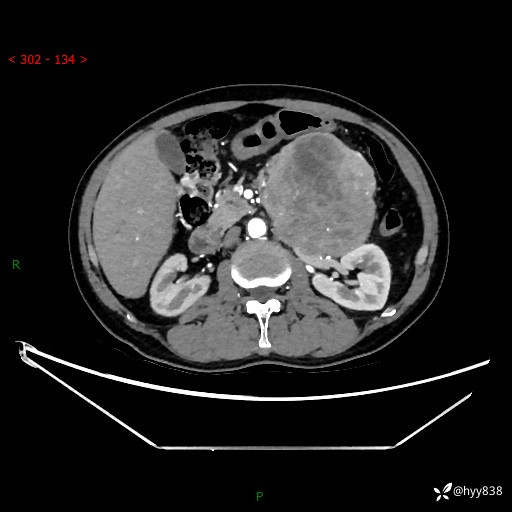

年龄:61岁

主诉:发现腹膜后肿瘤3天

腹部CT平扫+增强(动脉期+静脉期)